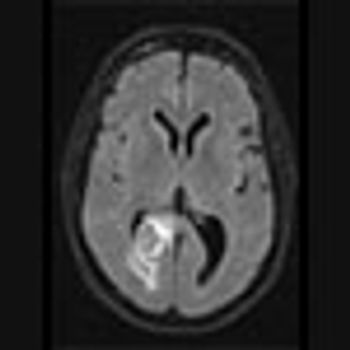

35-year-old female with prior history of breast carcinoma presented with frontal headaches.